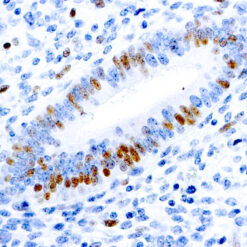

ERCC1

This antibody reacts with a 33-36 kDa protein known as ERCC1 (excision repair cross complementing) polypeptide. ERCC1 is required for nucleotide excision repair of damaged DNA and is homologous to RAD10. In mammalian cells, XPG cleaves 3’ of the DNA lesion while ERCC1-XPF complex makes the 5’ incision.

| Cellular Localization | Nuclear |

| Positive Control Tissue | Tonsil |